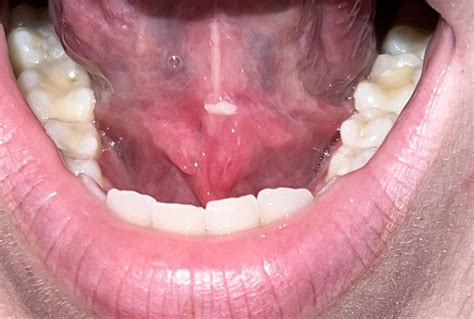

The underside of your tongue is composed of thin, delicate mucous membranes that are highly susceptible to trauma and inflammation. Identifying the source of the pain often involves looking for physical triggers or internal reactions.

• under your tongue pictures